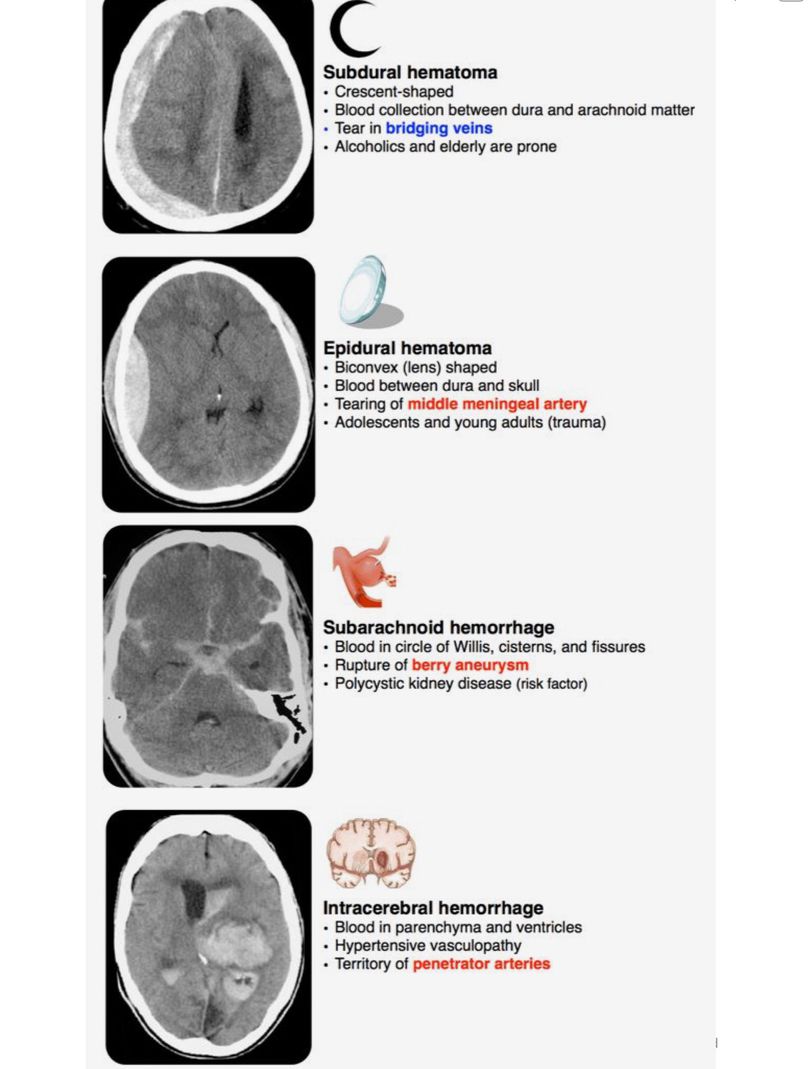

Hematoma, Hemorrhage

Hemorrhage

Hematoma